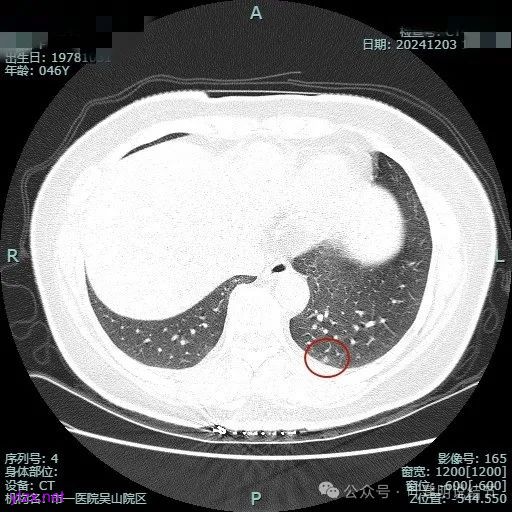

我们先来看2024年9月时的影像:

病灶1:

右下背段混合密度病灶,边上不太清爽,有片状淡磨玻璃影,实性部分密度较高。

感觉病灶有点晕征似的,表面不平,灶内不太致密。

有小血管进入,似有晕征。

离胸膜近但牵拉不明显,病灶边缘有细毛刺,较短且不太锐利。

边缘少许磨玻璃成分,血管进入明显。

瘤肺边界稍显不清。